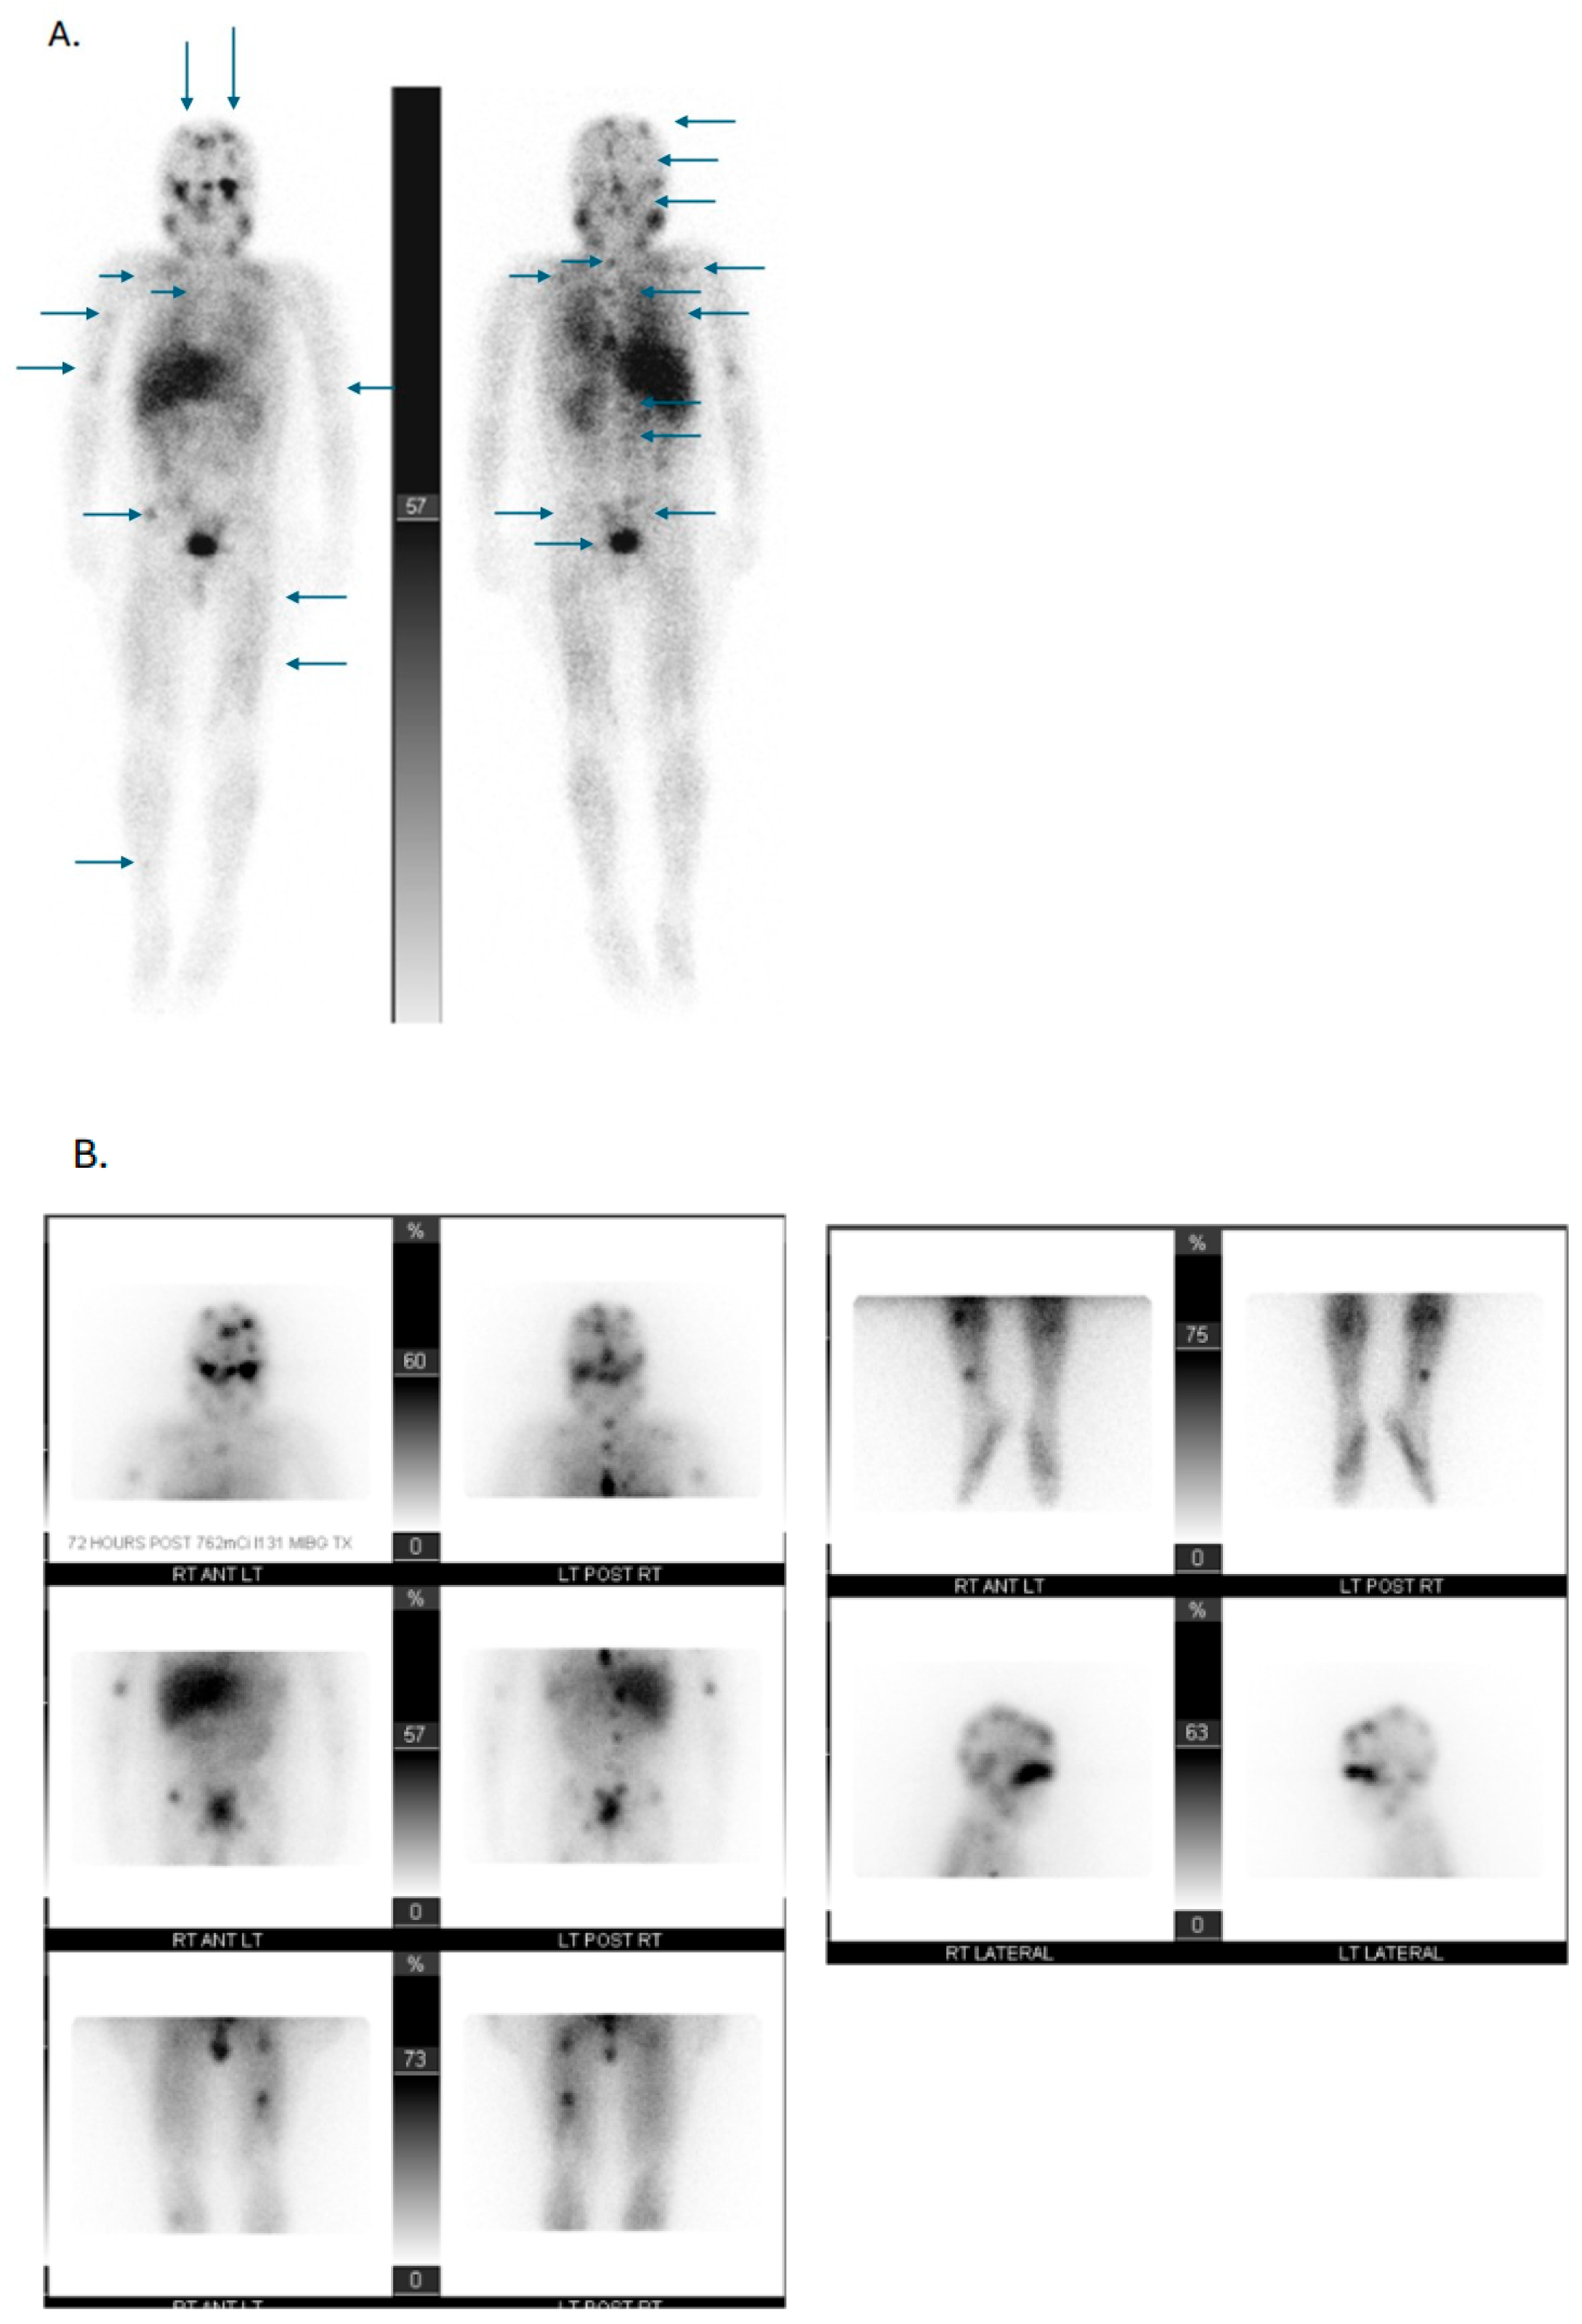

- Kong, G.; Hofman, M.S.; Murray, W.K.; Wilson, S.; Wood, P.; Downie, P.; Super, L.; Hogg, A.; Eu, P.; Hicks, R.J. Initial experience with gallium-68 DOTA-octreotate PET/CT and peptide receptor radionuclide therapy for pediatric patients with refractory metastatic neuroblastoma. J. Pediatr. Hematol. Oncol. 2016, 38, 87–96. [Google Scholar] [CrossRef]